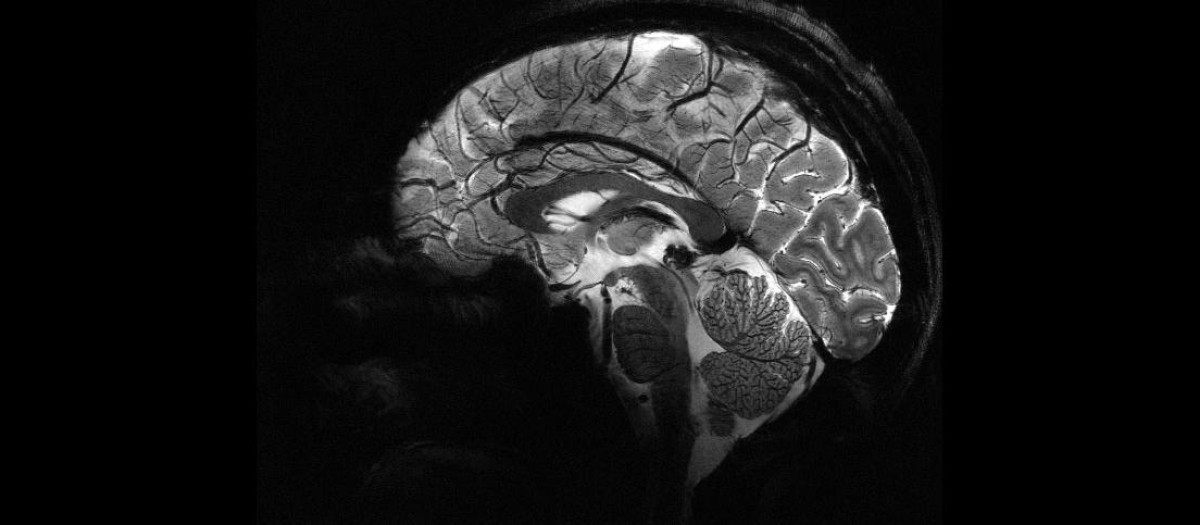

Imagen lateral del cerebro

El cerebro humano es, con diferencia, el órgano más complejo de nuestro cuerpo. Su arquitectura celular y su organización en redes neuronales permiten funciones tan sofisticadas como el lenguaje, la memoria o la toma de decisiones abstractas. Pero esa misma complejidad tiene un coste: el tejido cerebral posee una capacidad de regeneración muy limitada. A diferencia de la piel o el hígado, las neuronas que mueren rara vez se reemplazan.